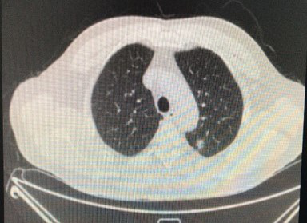

胸腹部CT(2017-10-18,本院):结肠癌术后,左肺上叶转移可能;肝脏、左肾囊肿

2017-10-18:

胸部+全腹部CT平扫增强(2018-02,本院):结肠癌术后,左肺上叶转移可能,较前减小

2018-2-26: